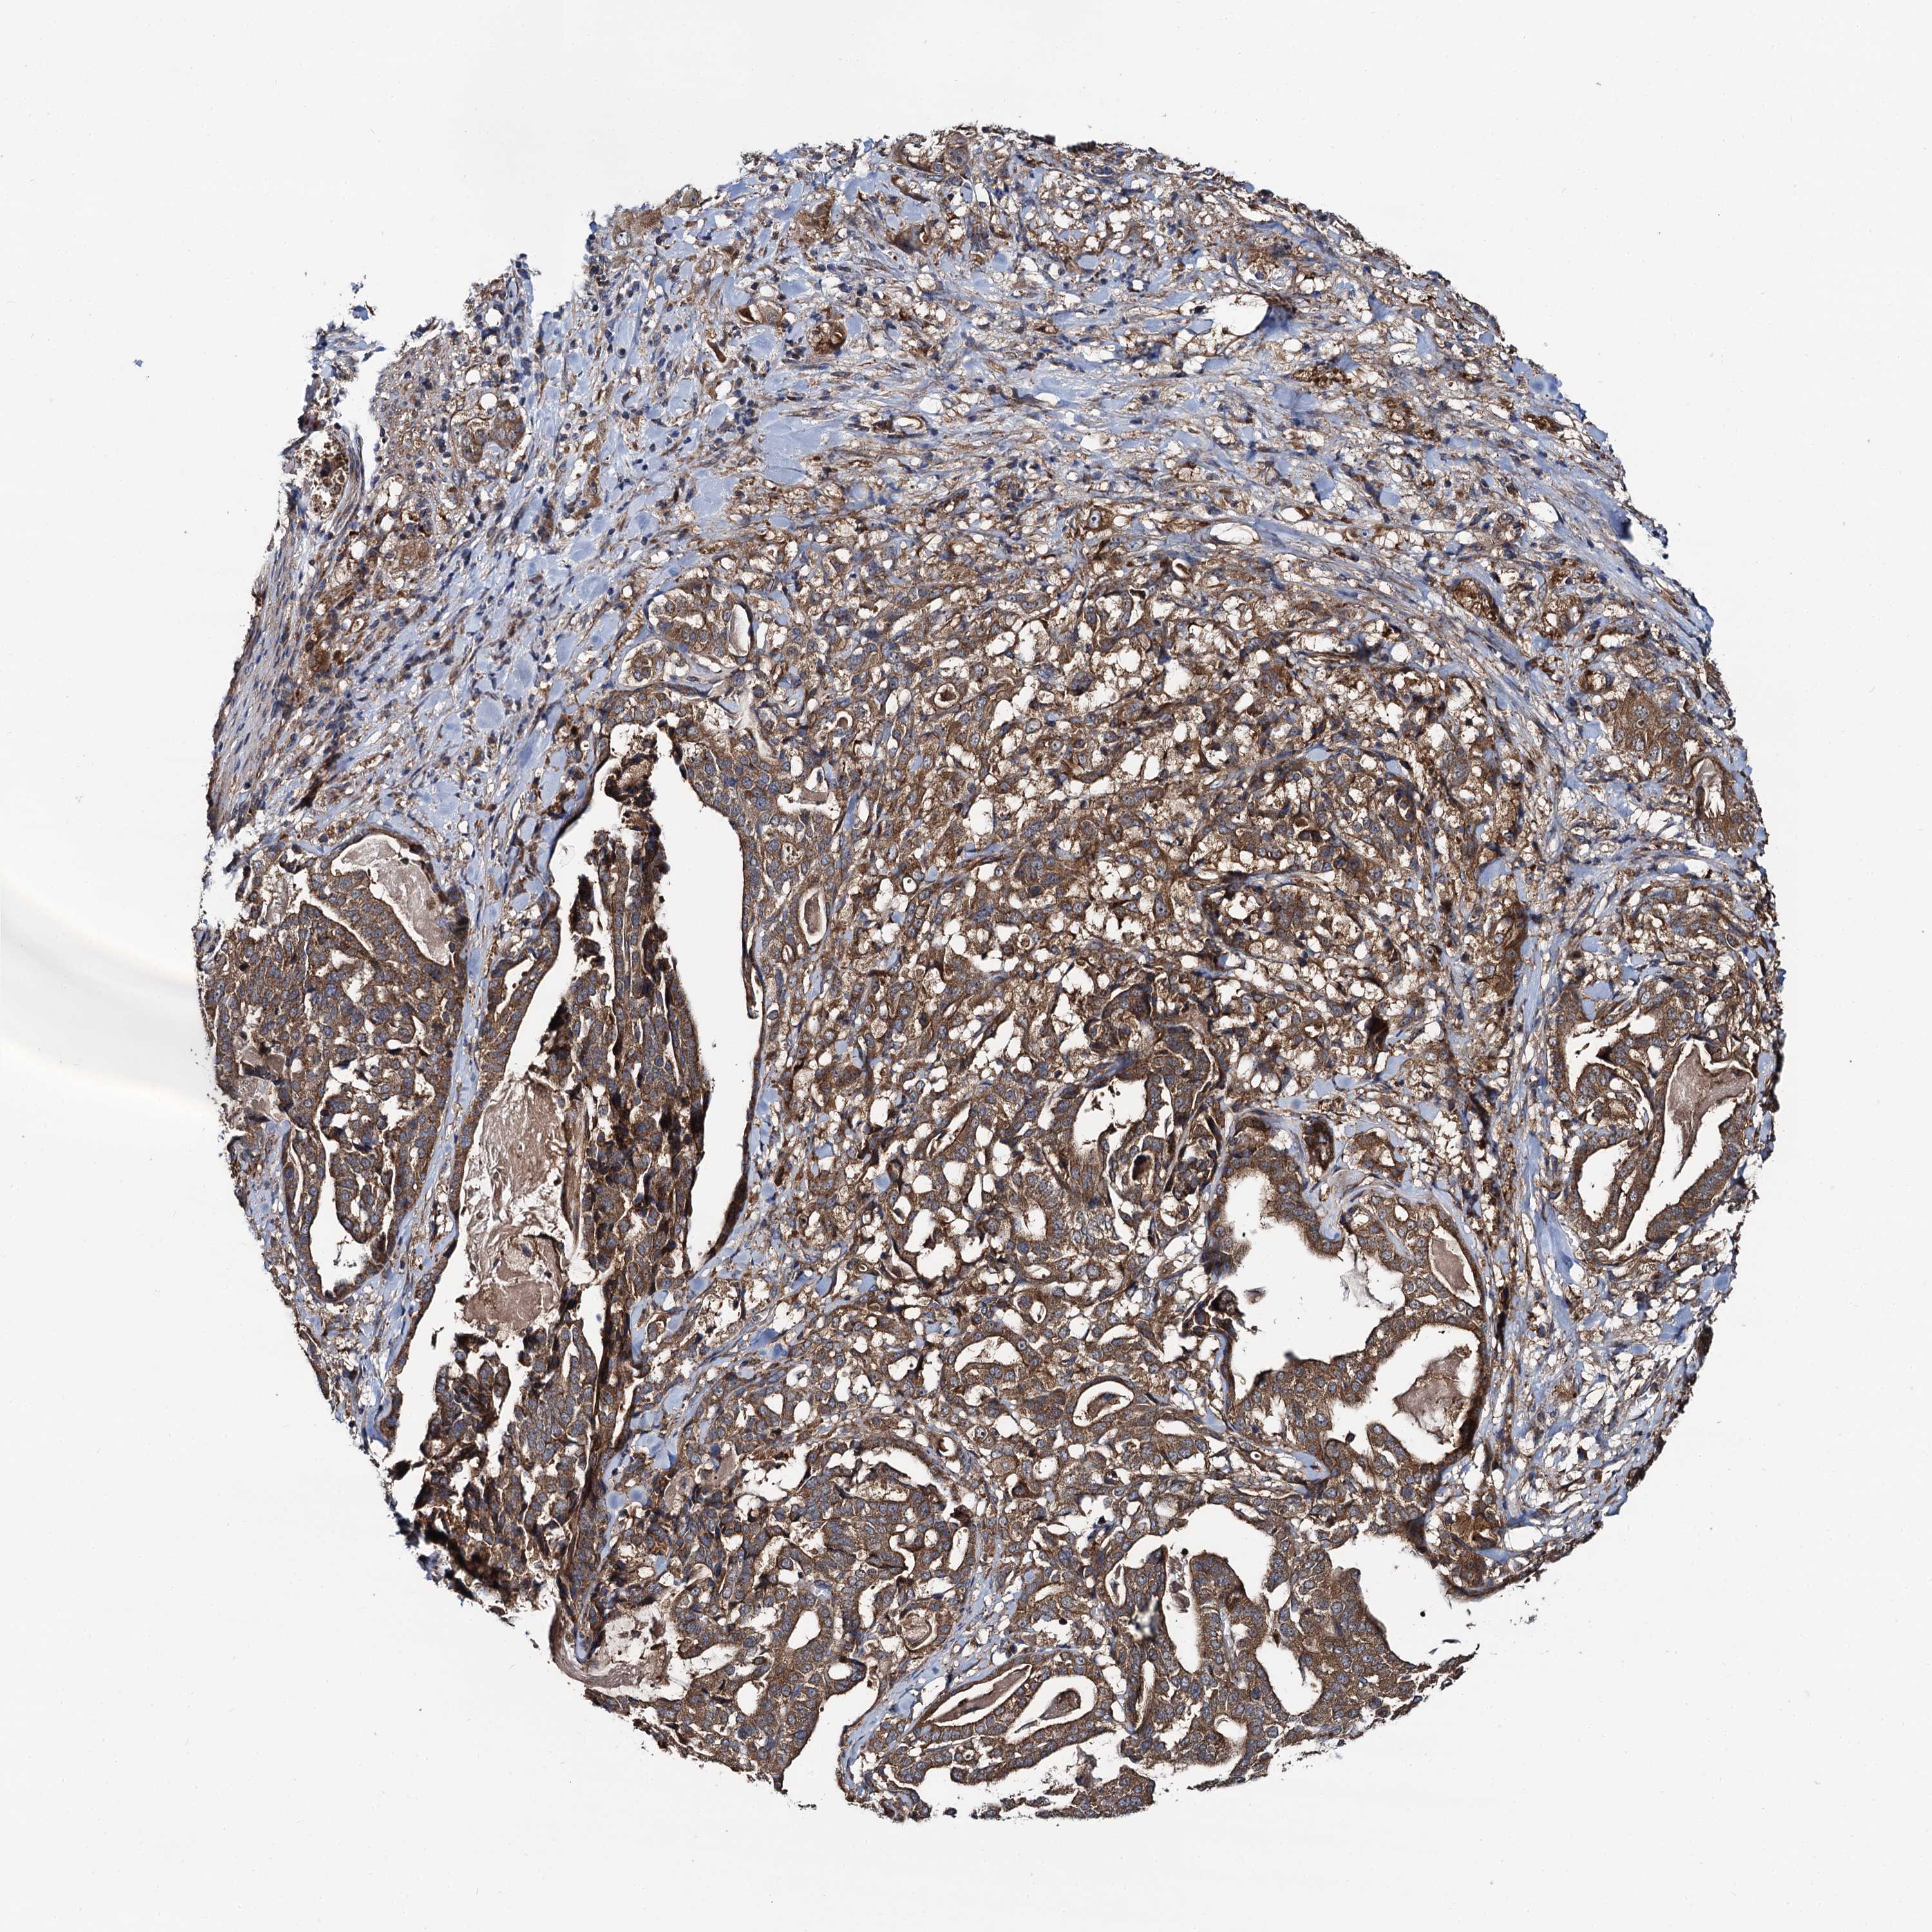

STOMACH CANCER - Protein expressioni

A mouse-over function shows sample information and annotation data. Click on an image to view it in a full screen mode. Samples can be filtered based on level of antibody staining by selecting one or several of the following categories: high, medium, low and not detected. The assay and annotation is described here.

Note that samples used for immunohistochemistry by the Human Protein Atlas do not correspond to samples in the TCGA dataset.

Antibody stainingi

Antibody staining in the annotated cell types in the current human tissue is reported as not detected, low, medium, or high, based on conventional immunohistochemistry profiling in selected tissues. This score is based on the combination of the staining intensity and fraction of stained cells.

Each image is clickable and will lead to virtual microscopy that enables deeper exploration of all samples and also displays staining intensity scores, fraction scores and subcellular localization as well as patient and tissue information for each sample.

Antibody HPA020873

Antibody HPA040413

Staining

High

Medium

Low

Not detected

Intensity

Strong

Moderate

Weak

Negative

Quantity

>75%

75%-25%

<25%

None

Location

Nuclear

Cytoplasmic/membranous

Cytoplasmic/membranous,nuclear

Adenocarcinoma, NOS

Adenocarcinoma, High grade